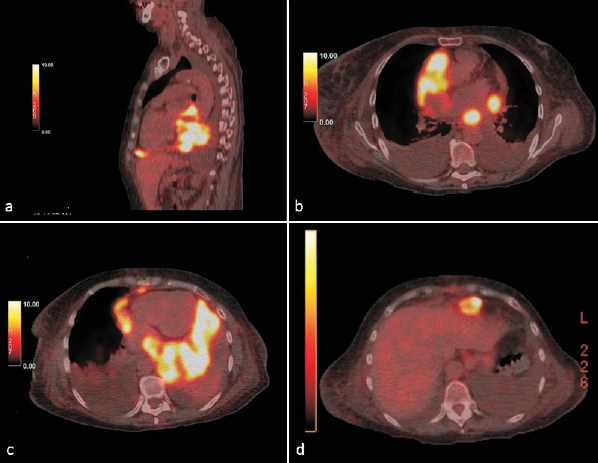

La inspección macroscópica de la masa reveló que se trataba de un tumor maligno, con alta probabilidad de que correspondiera a un linfoma. La tomografía de emisión de positrones (PET-TC) mostró una extensa masa hipermetabólica, localizada en la porción posterior del pericardio, con compresión de las cavidades cardíacas, principalmente de la aurícula izquierda, pero sin infiltrado miocárdico. A nivel anterior, en proximidad al diafragma, presentaba otra masa de similares características, a nivel pericárdico, de 22 mm. No se observó compromiso de médula ósea (figura 3).

Figura 3: PET-TC. a) Masa hipermetabólica sólida en el pericardio posterior y agrandamientos nodulares en el pericardio anterior en relación con el diafragma. b) y c) Extensión de la masa hacia la parte lateral del pericardio, pero sin infiltración miocárdica. d) Masa nodular anterior.